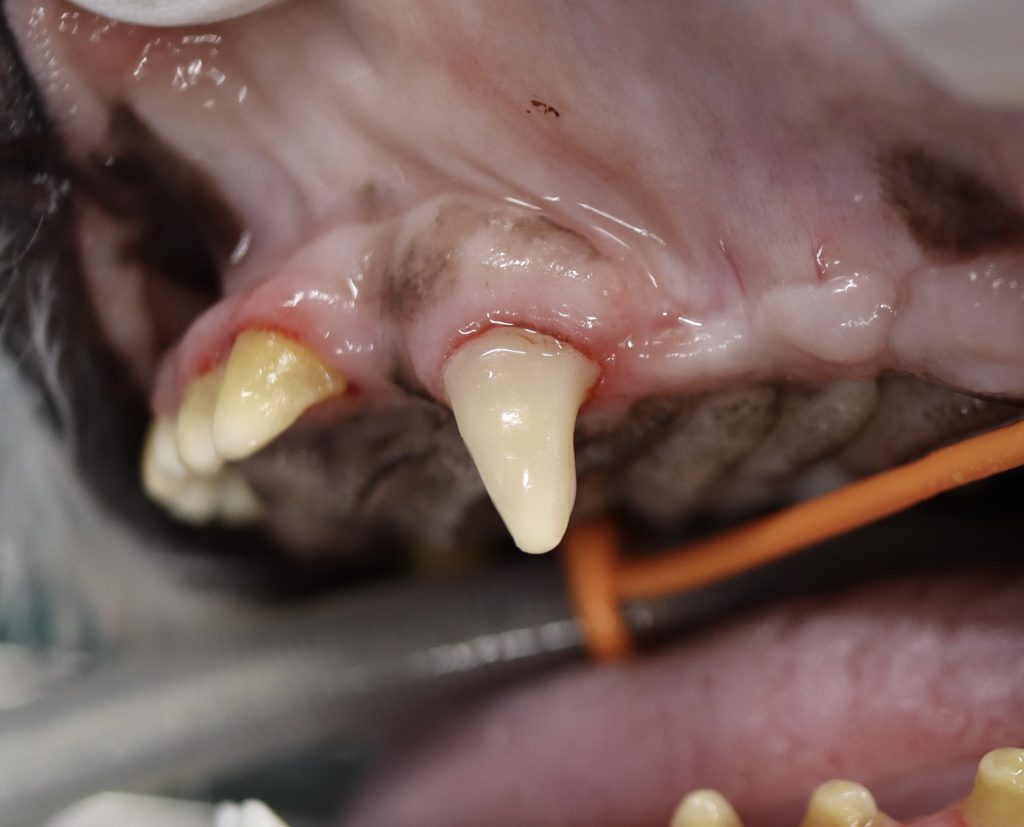

エナメル質欠損になると次のような症状が出ることがあります。

• 歯の表面が粗く、欠けている

• 歯の色が異常(茶色や黄色の変色)

• 歯が脆く、欠けやすい

• 歯垢や歯石の蓄積

肉眼的に歯の表面の異常を確認します。